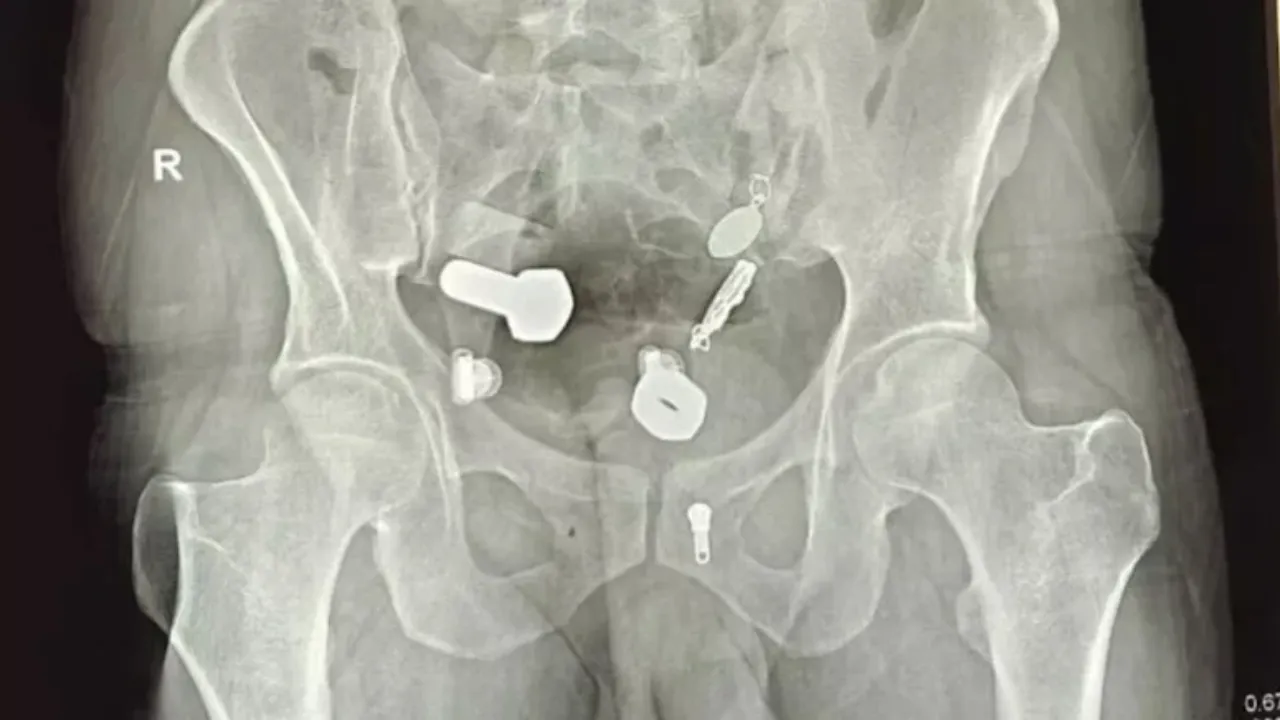

Hindistan'ın Jaipur şehrinde bir kişi, günlerdir mide ağrısı olduğunu, yemek yiyemediğini hatta su bile içemediğini söyleyerek hastaneye başvurdu. Doktorlar, çekilen filmlere baktıklarında ise neye uğradıklarını şaşırdılar. Hastanın yemek borusunda bir kol saati, bağırsaklarında ise çeşitli metal parçaları, cıvata, somun gibi cisimler vardı.

Doktorlar, ilk olarak endoskopi yaparak cisimleri çıkarmak istedi fakat bu yöntem başarılı olmadı. Hasta ameliyata alındı. 3 saat süren ameliyatın ardından hastanın içindeki metal cisimler çıkarıldı.